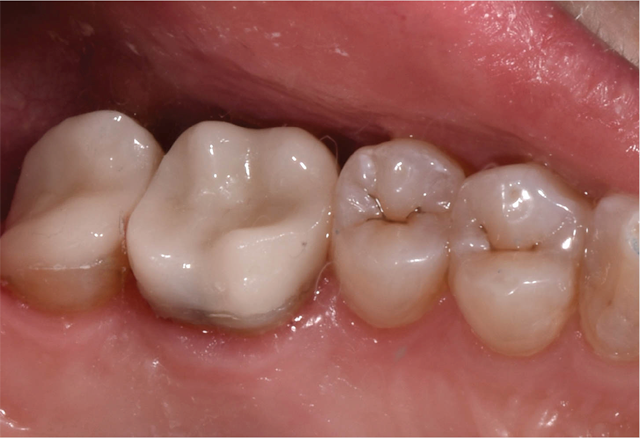

A 50-year-old female with no significant medical history presents for same-day, all-ceramic, full coverage onlay restorations on tooth No. 14 and No. 15. Existing restorations include No. 14OL and No. 15DO defective composites with open margins and recurrent caries (Fig. 1). The patient reports infrequent cold sensitivity localized to No. 14 and No. 15.

Fig. 1 Fig. 2